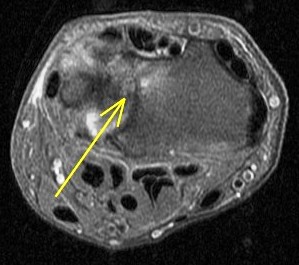

Ulnar impingement syndrome